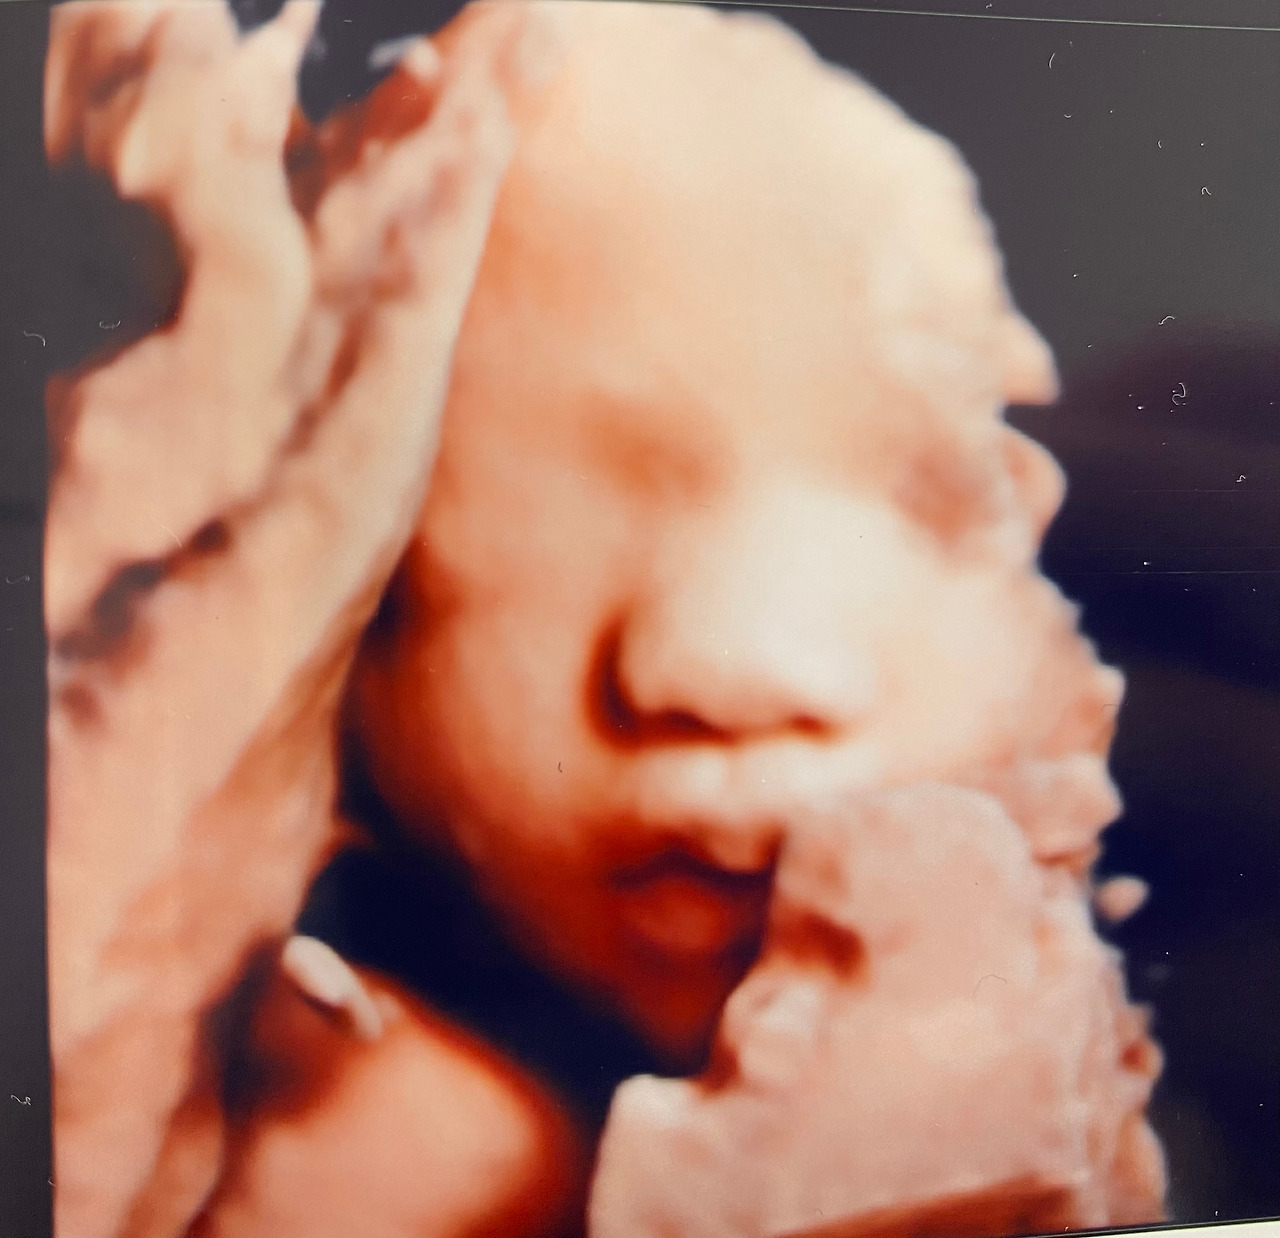

눈은 감고 있어서인지 안보였고, 코는 보자마자 '내 코인데!' 싶었고 인중과 입술은 넘나넘나 귀여웠다. ㅠㅠ

근데 임신 초중반에 흑백 초음파로 옆모습을 봤을 때는 분명 콧대가 높고 잘 보여서 코는 주호를 닮았다 싶었는데 몽똥하니 내 코가 되어있었다. 코는 주호 닮지...ㅎㅎ 주호도 보자마자 내 코라며 ㅋㅋㅋ

인중은 또렷하고 조그마한 입술은 윗입술은 M자로 뾰족하고 아랫입술은 도톰하니 넘나 이쁘고 귀여웠다.

기계가 좋아서인지는 몰라도 피부도 넘 깨끗하니 뽀얗게 넘넘 이뻤다.

이렇게 사람다운(?) 사진을 보고나니 주호는 실감이 나는 듯 보였다. 일반 2D 초음파 사진은 볼때마다 자기는 잘 모르겠다고 했었는데 이번에 얼굴을 보고는 이렇다 저렇다 말도 많고 지금까지의 반응 중 가장 텐션업 된 모습이었다.

쌩쌩이(210928_02).jpg